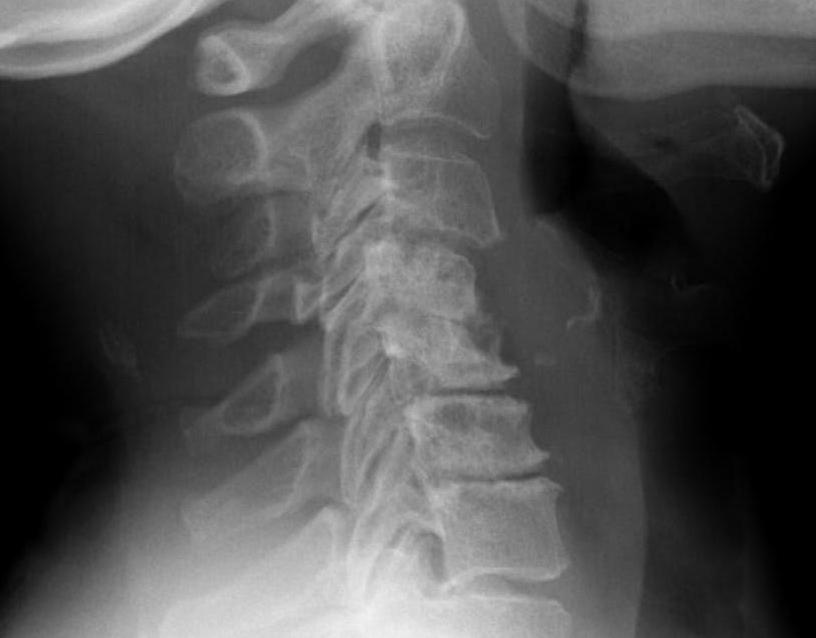

Subaxial Subluxation (SAS)

Definition

Anterior subluxation of one vertebral body on another

Results in spinal stenosis

Diagnosis

A. Instability on Flexion / Extension views

- > 3mm

- > 11o

Anterior subluxation of C3 on C4

B. Space available for cord / SAC

- subaxial canal diameter on lateral

- < 13 mm high incidence neurology

Pathology

Facet erosions / ligament incompetence

May see at multiple levels with stepladder type deformity & kyphosis

Can occur beneath previous cervical fusions including C1/C2